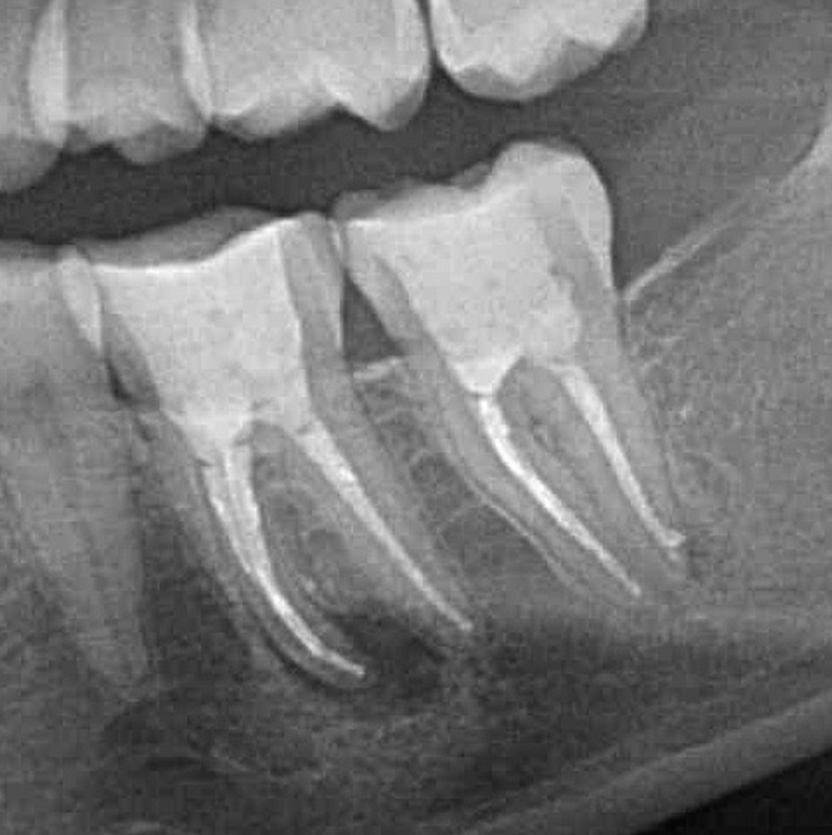

Wenn ein Zahn immer wieder Schmerzen bereitet, ist die Ursache oft eine Entzündung des Nervs, meist ausgelöst durch tiefe Karies. Mit einer Wurzelkanalbehandlung und dichter Wurzelfüllung lässt sich der Zahn aber in den meisten Fällen doch noch erhalten. Durch moderne Behandlung mit hoch flexiblen Nickel-Titan-Instrumenten und neuartigen Maschinensysteme lassen sich heute Zähne erhalten, die man früher hätte entfernen müssen.

Weiterhin wird in unserer Praxis mit Lupenbrille, elektronischer Längenbestimmung des Wurzelkanals und speziellen Ultraschallgeräten bei der Aufbereitung gearbeitet. Außerdem bieten wir auch den Austausch (Revision) von alten unvollständigen Wurzelfüllungen an. Mit all diesen Maßnahmen schaffen wir die optimalen Voraussetzungen, dass Sie ihren eigenen Zahn noch viele Jahre behalten können .